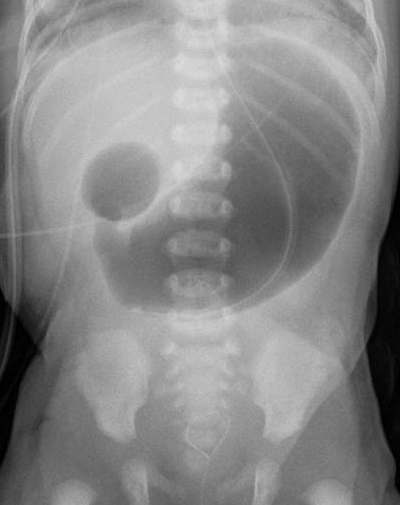

double bubble sign

duodenal atresia

polyhydramnios, bilious vomiting within first 24 hours of life

dudodenal atresia (compare with pyloric stenosis)